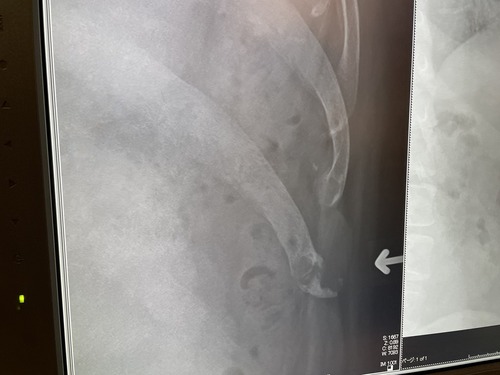

さて、翌朝、電話をしたのだが、いよいよ声が何言ってるか分からん状態。こっちは一所懸命、声を張り上げているのだが、電話越しには雑音以外に聞こえなかったらしい。埒が明かないので、嫁はんを叩き起こして電話させ、1000時に検査を受ける事になった。検査の方法は、23年の9月の時と同様、車の窓越しに検査棒を鼻に突っ込まれるやり方で、結果はまさかのコロナ陽性。インフルはAもBも陰性という事だった。前回同様に、ゾコーバとカロナール、そして鼻や喉の薬を処方された。違うのは、前回はゾコーバは政府持ちだったが、今回は自分持ちで、保険適用でも1.6万円した。